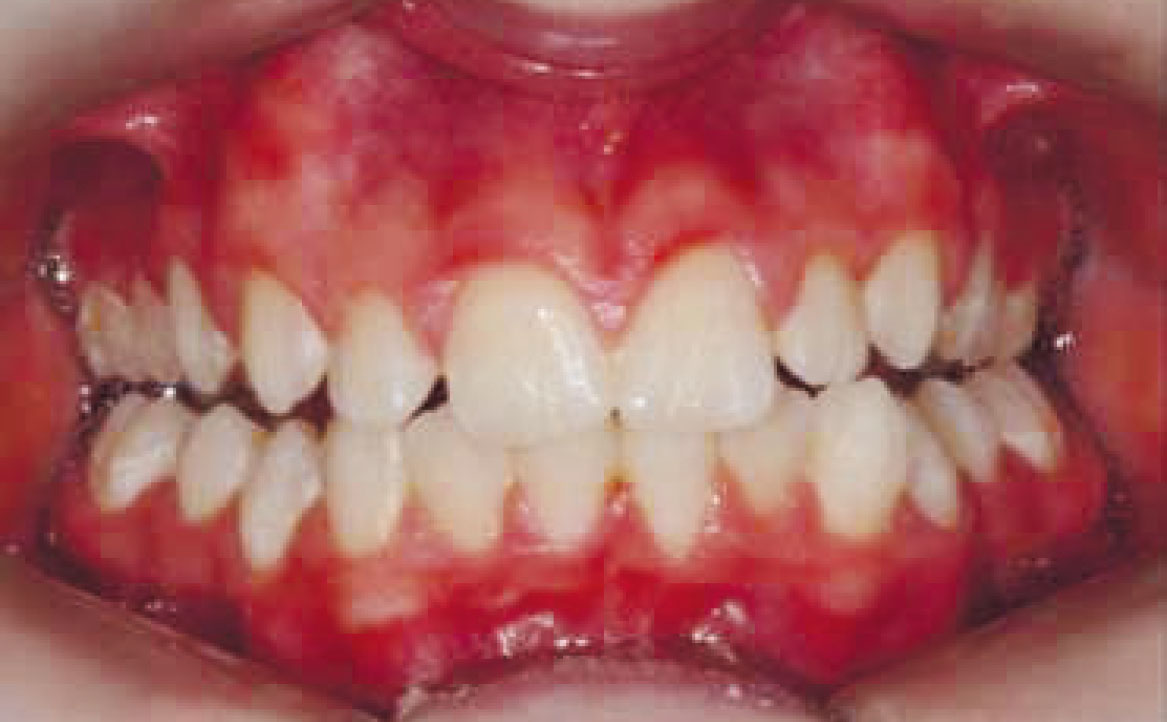

Paziente di genere femminile di otto anni affetta da una malocclusione di classe II sia dentale che scheletrica, associata a una condizione di retrusione mandibolare e contrazione dell’arcata superiore. Non si rilevano problemi dentali significativi.

La paziente viene condotta all’osservazione dai genitori al fine di correggere la problematica estetica legata al sorriso gengivale.

Viene eseguita la consueta raccolta dei records: fotografie intra ed extra orali, modelli e indagini radiografiche di primo livello (OPT e teleradiografia latero-laterale) (fig. 2-11).

L’esame clinico e strumentale consentono di porre diagnosi di malocclusione di classe II di natura scheletrica, associata a retrusione mandibolare. In questa condizione, la mandibola mostra dimensioni e volume inferiori rispetto ai valori medi per età scheletrica e sesso.